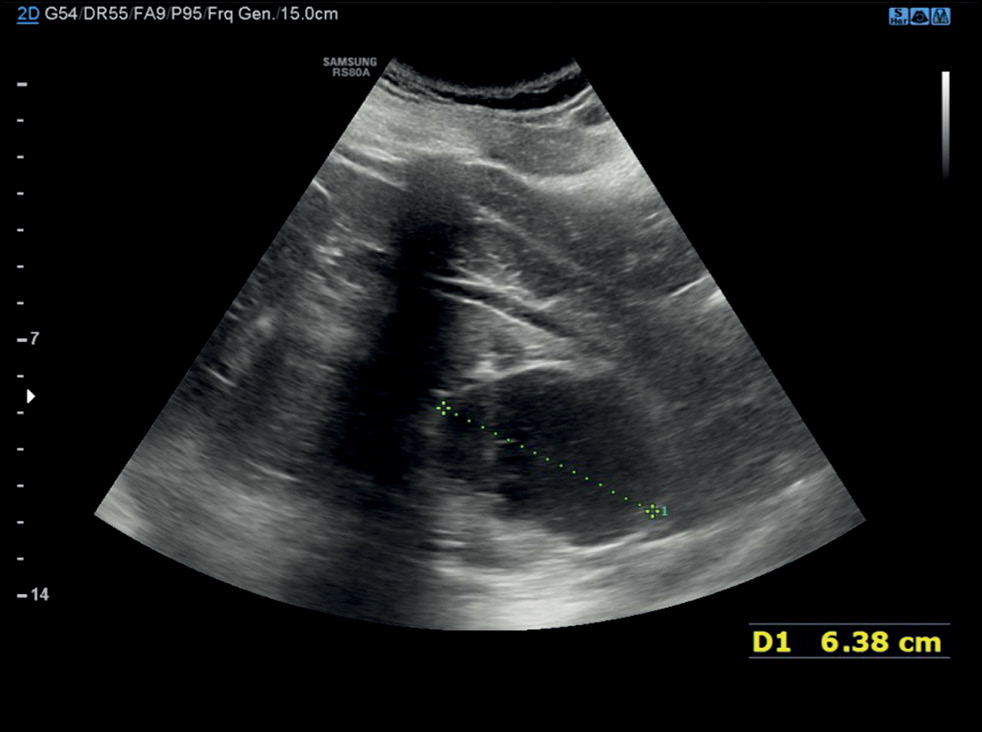

Случай спонтанного разрыва печени и роль визуализации: от компьютерной томографии до интервенционного лечения

Разрыв паренхимы печени — редкое, но потенциально смертельное состояние, которое может быть вызвано травмой, ятрогенными факторами, спонтанными причинами и так далее. В данной статье описан клинический случай, в котором представлены диагностические и терапевтические меры, применённые в ходе лечения пациентки со спонтанным разрывом паренхимы печени. Пожилая женщина поступила в отделение неотложной помощи с болью в животе диффузного характера. После клинического обследования ей была проведена компьютерная томография. По результатам первой компьютерной томографии не выявили полномасштабного разрыва паренхимы. Из-за неоднозначности данных, указывающих на то, что боль в животе могла быть вызвана почечной или желчной коликой, поставить ранний диагноз было очень проблематично. В паренхиме печени было обнаружено лишь несколько гиподенсных образований овальной формы, наполненных жидкостью повышенной плотности. Однако боль сохранялась в течение нескольких дней, и ввиду ухудшения состояния пациентки были проведены дополнительные рентгенологические исследования, по результатам которых выявили разрыв паренхимы печени. Это потребовало в дальнейшем применения метода артериографии, а также длительного пребывания в стационаре до клинического разрешения.